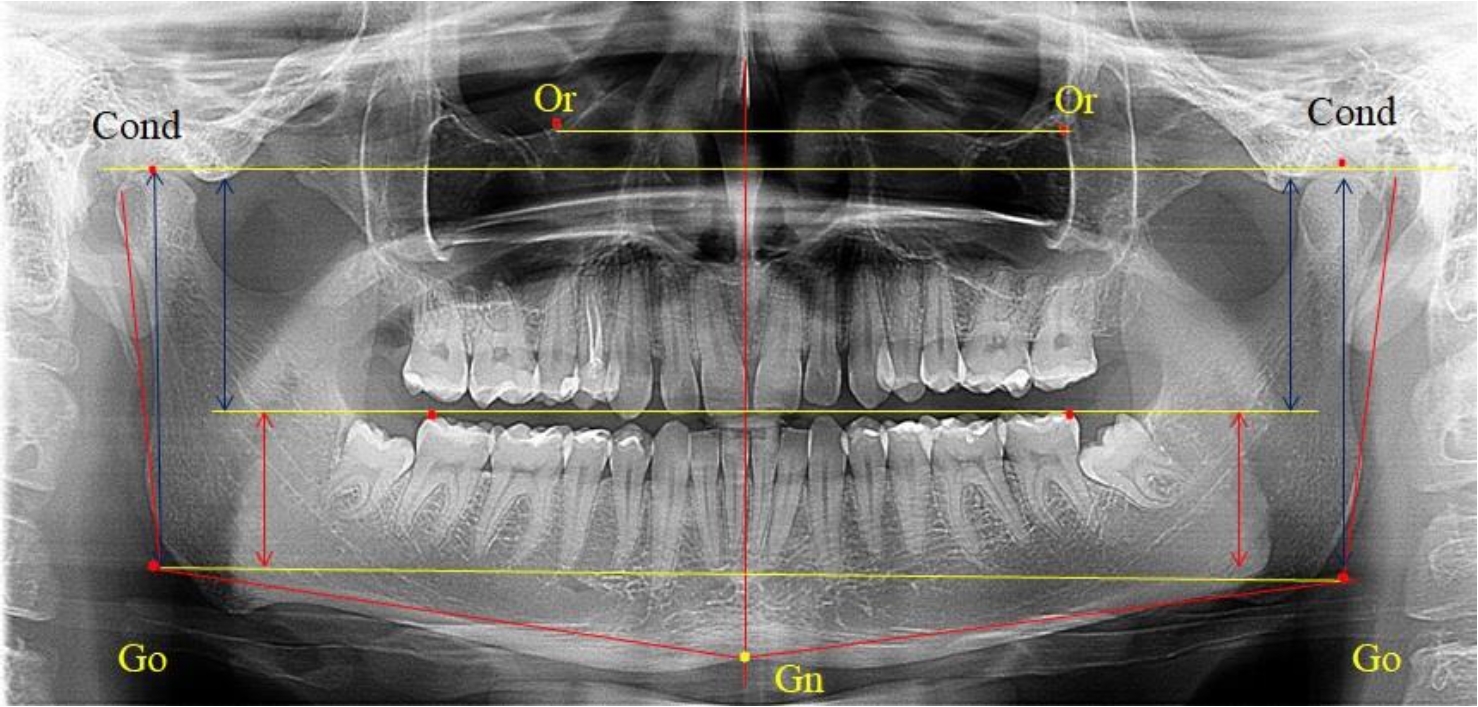

На боковых телерентгенограммах определяли положение верхней точки суставной головки Cond. Касательные линии к ветви и телу нижней челюсти пересекались в точке, которую в клинической практике обозначают как точка угла нижней челюсти или точка гонион Go. Точкой hPOcP обозначали дистальный бугорок нижнего второго моляра вблизи окклюзионного контура коронки, через нее от межрезцовой точки проводили окклюзионную линию, ее продолжали до задней части ветви челюсти. Высоту ветви измеряли как расстояние от угла нижней челюсти до вершины суставной головки Go-Cond. Общую высоту ветви условно делили на 2 части, ее границей служила окклюзионная линия. Верхнюю часть обозначали как окклюзионно-суставная, а нижнюю – как окклюзионно-гониональная.

На ортопантомограмме использовали аналогичные суставные точки Cond на каждой стороне, их соединяли между собой суставной линией Cond-Cond.

Касательная к ветви нижней челюсти соединяла выступающие точку. При построении касательной к телу челюсти проводили в обе стороны линии от точки Gn, расположенной в нижней центральной части подбородочного симфиза, до выступающей нижней точки угла челюсти. Касательные линии при пересечении определяли конструктивную точку гонион Go. Соединение гониональных точек определяло положение гониональной линии Go-Go. При соединении окклюзионных точек hPOcP получали окклюзионную горизонталь (рис. 1). Измеряли расстояние между горизонталями в области ветвей нижней челюсти. Статистический анализ проводили в программе Microsoft Excel. Составляли вариационные ряды с последующим расчетом среднего значения, стандартного отклонения и ошибки среднего ±m. Также оценивали максимальные и минимальные значения величин. Определи относительные величины соотношения верхней и нижней частей ветви нижней челюсти.

Рис. 1. Метод измерения высоты ветви нижней челюсти на телерентгенограмме (а) и ортопантомограмме (б)

Во 2-ю подгруппу был включен 21 комплект телерентгенограмм и ортопантомограмм [или (28,38 ± 5,24) %], на которых средняя величина отношения верхней части ветви к нижней составляла 1,63 ± 0,03, что было достоверно меньше показателя, полученного по группе в среднем и в 1-й подгруппе.

Визуально параметры ветви отличались от первой группы (рис. 3).

Рис. 3. ОПТГ пациента 2-й группы с уменьшенным коэффициентом соотношения частей ветви нижней челюсти

Высота ветви составляла (62,75 ± 1,42) мм и достоверных различий по этому показателю не отмечено. Максимальная высота была 73 мм, а минимальная – 55 мм. Высота верхней части составляла (38,81 ± 0,76) мм, что было достоверно меньше, чем у людей 1-й подгруппы.

В то же время высота нижнего отдела ветви была (23,94 ± 0,73) мм, и показатель отличался в большую сторону по сравнению с аналогичным размеров в 1-й подгруппе.